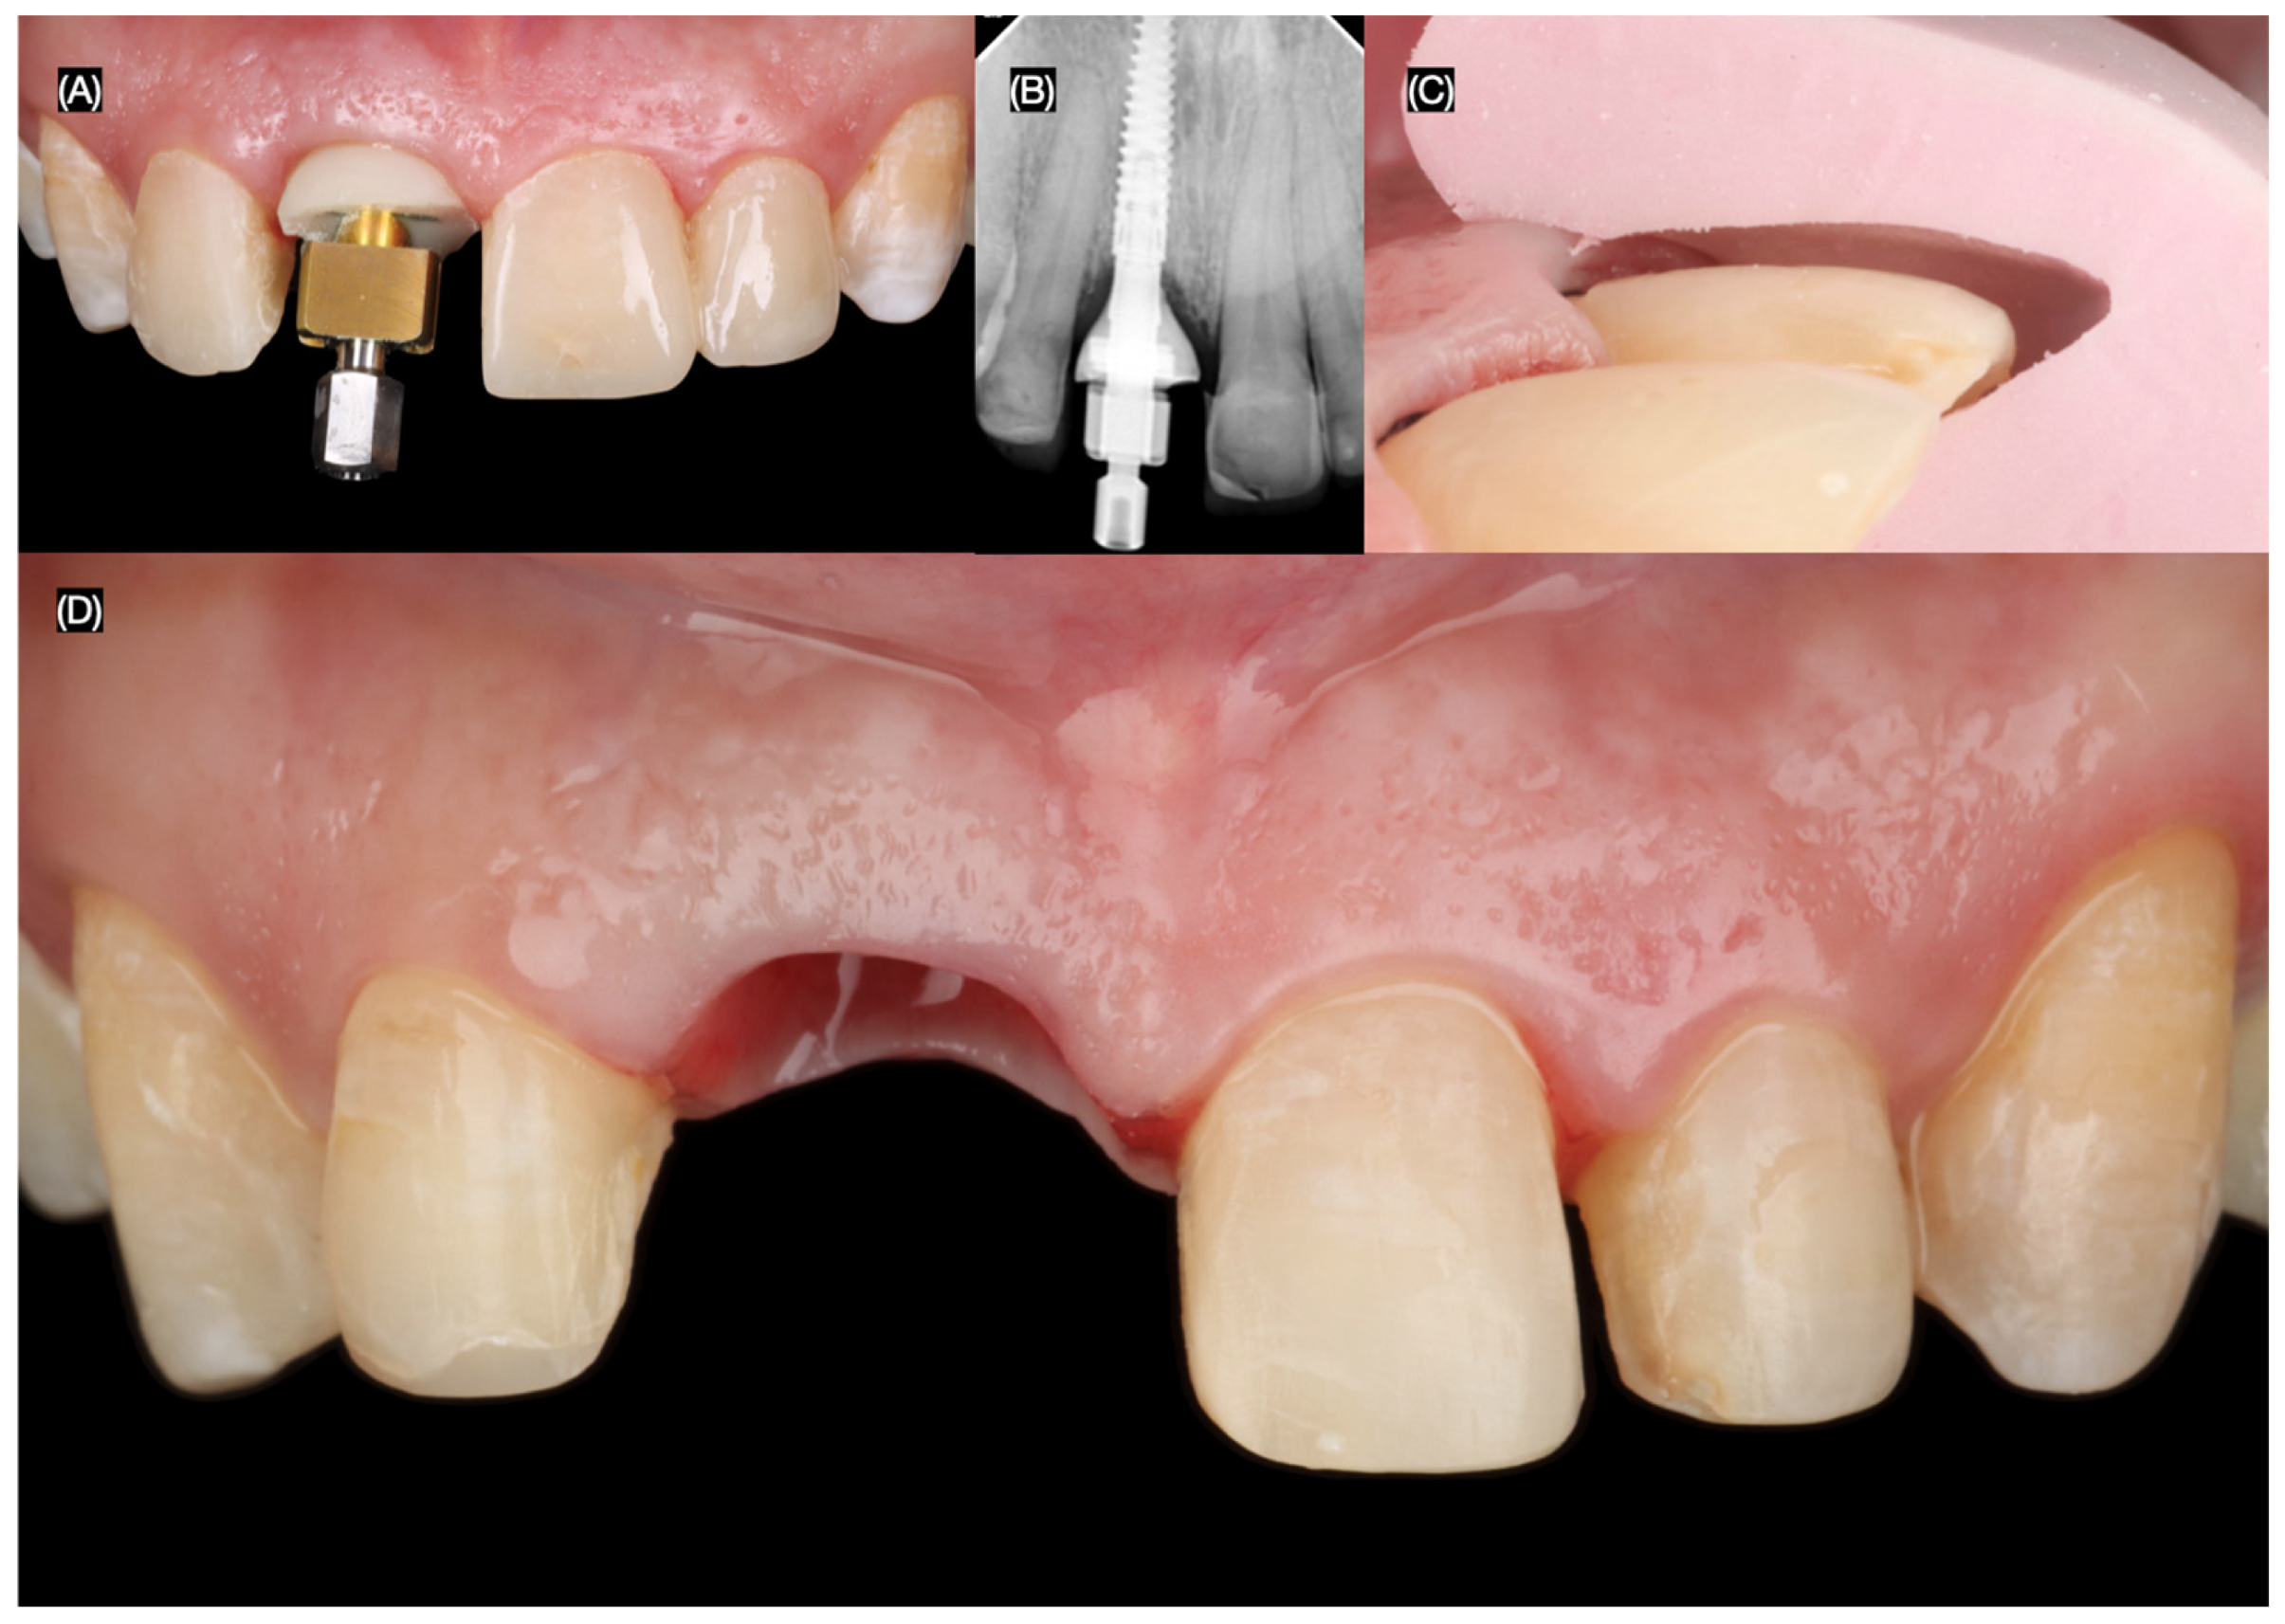

Figure 4.

Flapless atraumatic tooth extraction. (A) Desmotomes insertion, (B) luxation of root, (C) extraction, and (D) incisal view after extraction.

The maxillary right central incisor was extracted atraumatically, preserving the surrounding bone and soft tissues. An immediate implant (MISC C1, 3.30 mm × 13 mm, MIS Implant, Misgav, Israel) was placed using a surgical guide, ensuring precise positioning and primary stability (Figure 4 and Figure 5).